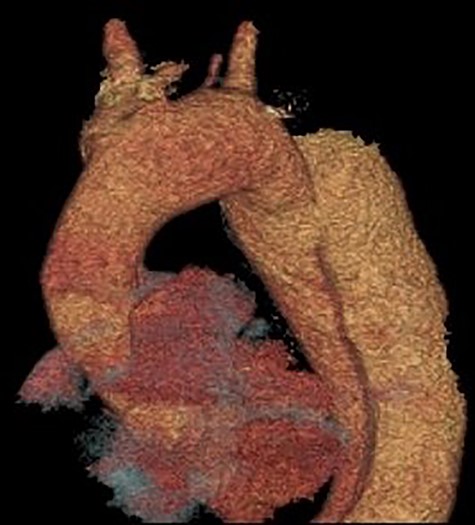

3D reconstruction of the CT scan demonstrating the four-vessel arch configuration with the aberrant left vertebral artery located in the Zone 2 region.

A 52-year-old gentleman presented to our institution with a previous history of TBAD (diagnosed 3 years previously), which was managed conservatively. His comorbidities included hypertension and excision of a left frontal cavernoma with no family history of aortic aneurysm or dissection. Following his initial presentation of chest pain, the patient had remained asymptomatic and stable. Surveillance management was initially instituted and the case discussed at the aortic multidisciplinary meeting. Due to retrograde extension of the TBAD into the distal arch, persistence of the false lumen, increasing descending aortic dimensions (6.0 cm) and an anomalous left vertebral artery originating from the aortic arch, the patient proceeded to aortic arch surgery and antegrade deployment of the stent into the descending aorta with a FET graft (Figs 1, 2). Preoperative coronary angiography and transoesophageal echocardiography revealed no coronary artery disease and a competent trileaflet aortic valve with preserved left ventricular function.